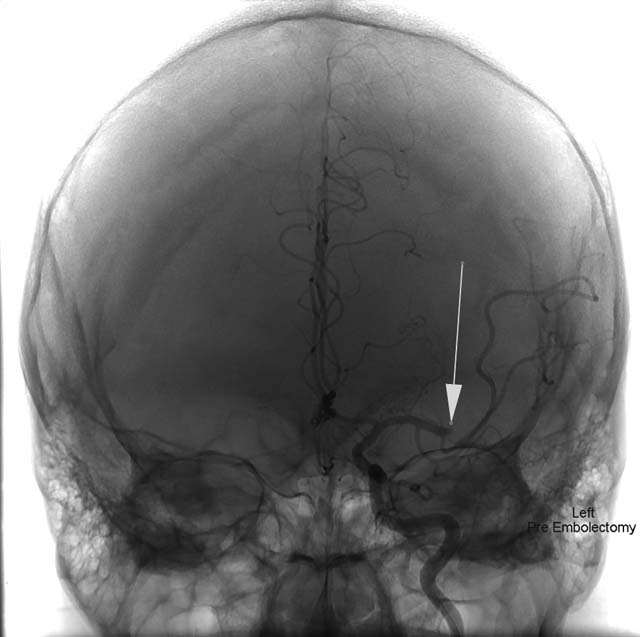

Immediatamente vengono chiamati i neurochirurghi delle Molinette e Mauro Bergui esegue una delicata trombectomia: entrando con un catetere venoso dall’inguine arriva fino al cervello dove rimuove il trombo e posiziona uno stent. Intervento riuscito: ora la bimba e’ sveglia, ha ripreso a parlare e a mangiare ed e’ ricoverata nel reparto di pediatria universitaria del Regina Margherita. Ha ancora qualche problema al lato destro del corpo ma i medici confidano che con la fisioterapia possa riprendersi completamente.